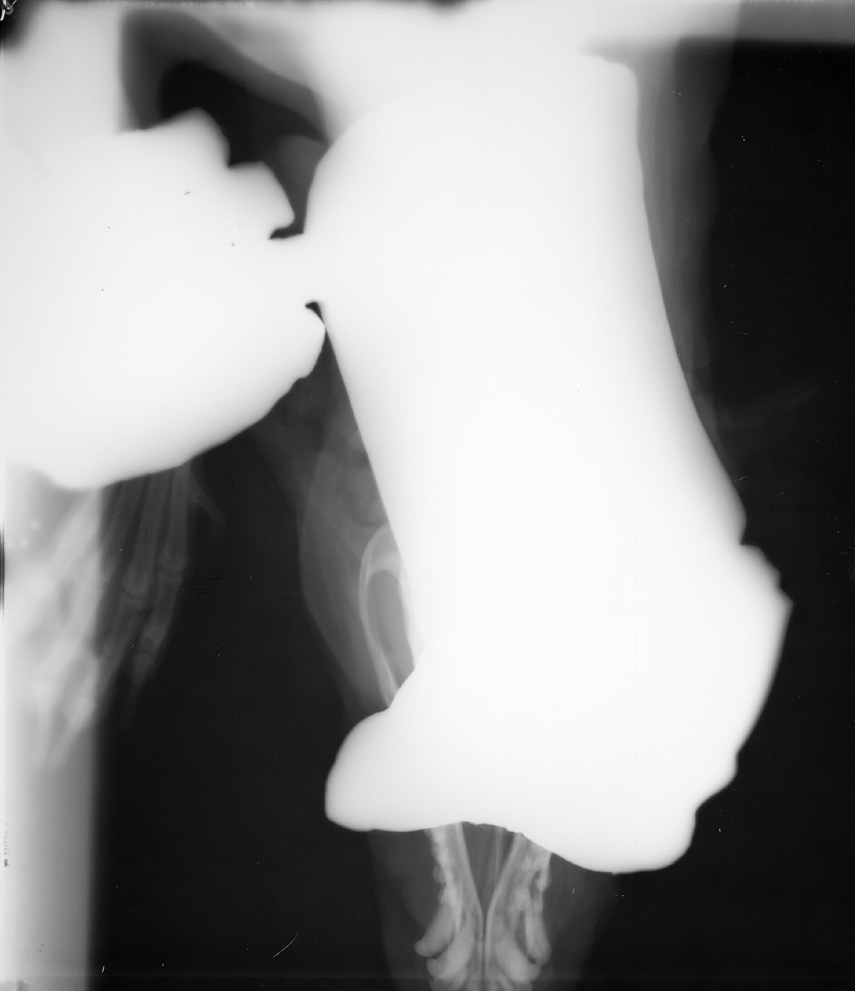

Hand in Primary Beam

Even with a glove this is unacceptable. Gloves DO NOT protect you from the primary x-ray beam - only from scatter radiation.